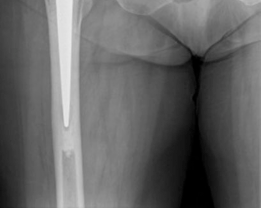

The Rationale for a Hybrid Construct

The term "Hybrid Primary Hip Arthroplasty" refers to the use of an uncemented (press-fit) acetabular component combined with a cemented femoral stem.

- Cemented Femoral Stem: The use of cemented femoral stems in the elderly trauma population is strongly supported by contemporary orthopedic literature. The WHiTE 3 trial and various national joint registry data have conclusively shown that uncemented stems in elderly patients with Dorr B or C bone (osteopenic/osteoporotic) carry a significantly higher risk of intraoperative and early postoperative periprosthetic femoral fractures. Cemented stems provide immediate, rigid fixation, bypassing the need for biologic ingrowth, and distribute stress more evenly across the weakened proximal femur.

Therefore, a hybrid construct offers the optimal balance: minimizing the risk of periprosthetic femoral fracture while maximizing the longevity and stability of the acetabular reconstruction.